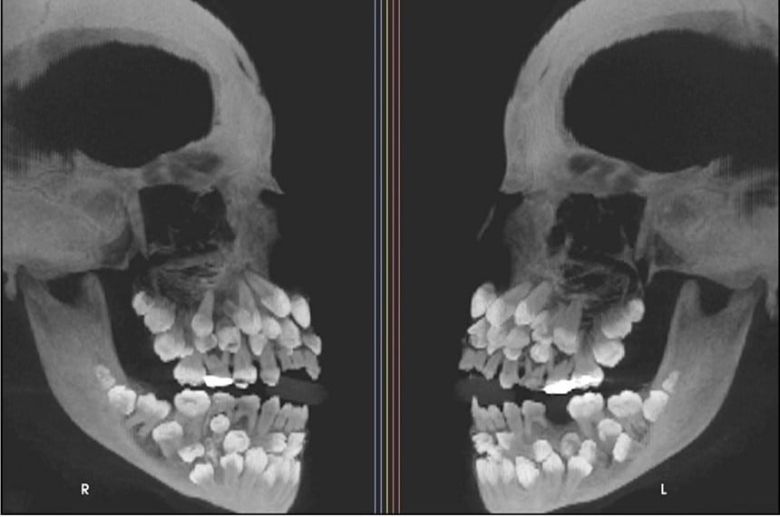

브라질의 한 소녀 입 안에서 치아 81개가 발견됐다./미국 치과교정·악안면외과학회지 |

최근 VN익스프레스 등에 따르면 브라질에 사는 11세 소녀의 구강 엑스레이 결과 입 안에서 유치 18개와 영구치 32개, 과잉치 31개 등 총 81개 치아가 발견됐다.

연구팀은 정밀 영상 검사를 통해 치아의 정확한 위치를 파악했다. 또 과잉치증이 유전 질환과 연관된 것은 아닌지 확인하기 위해 관련 유전자 검사도 함께 진행했다.